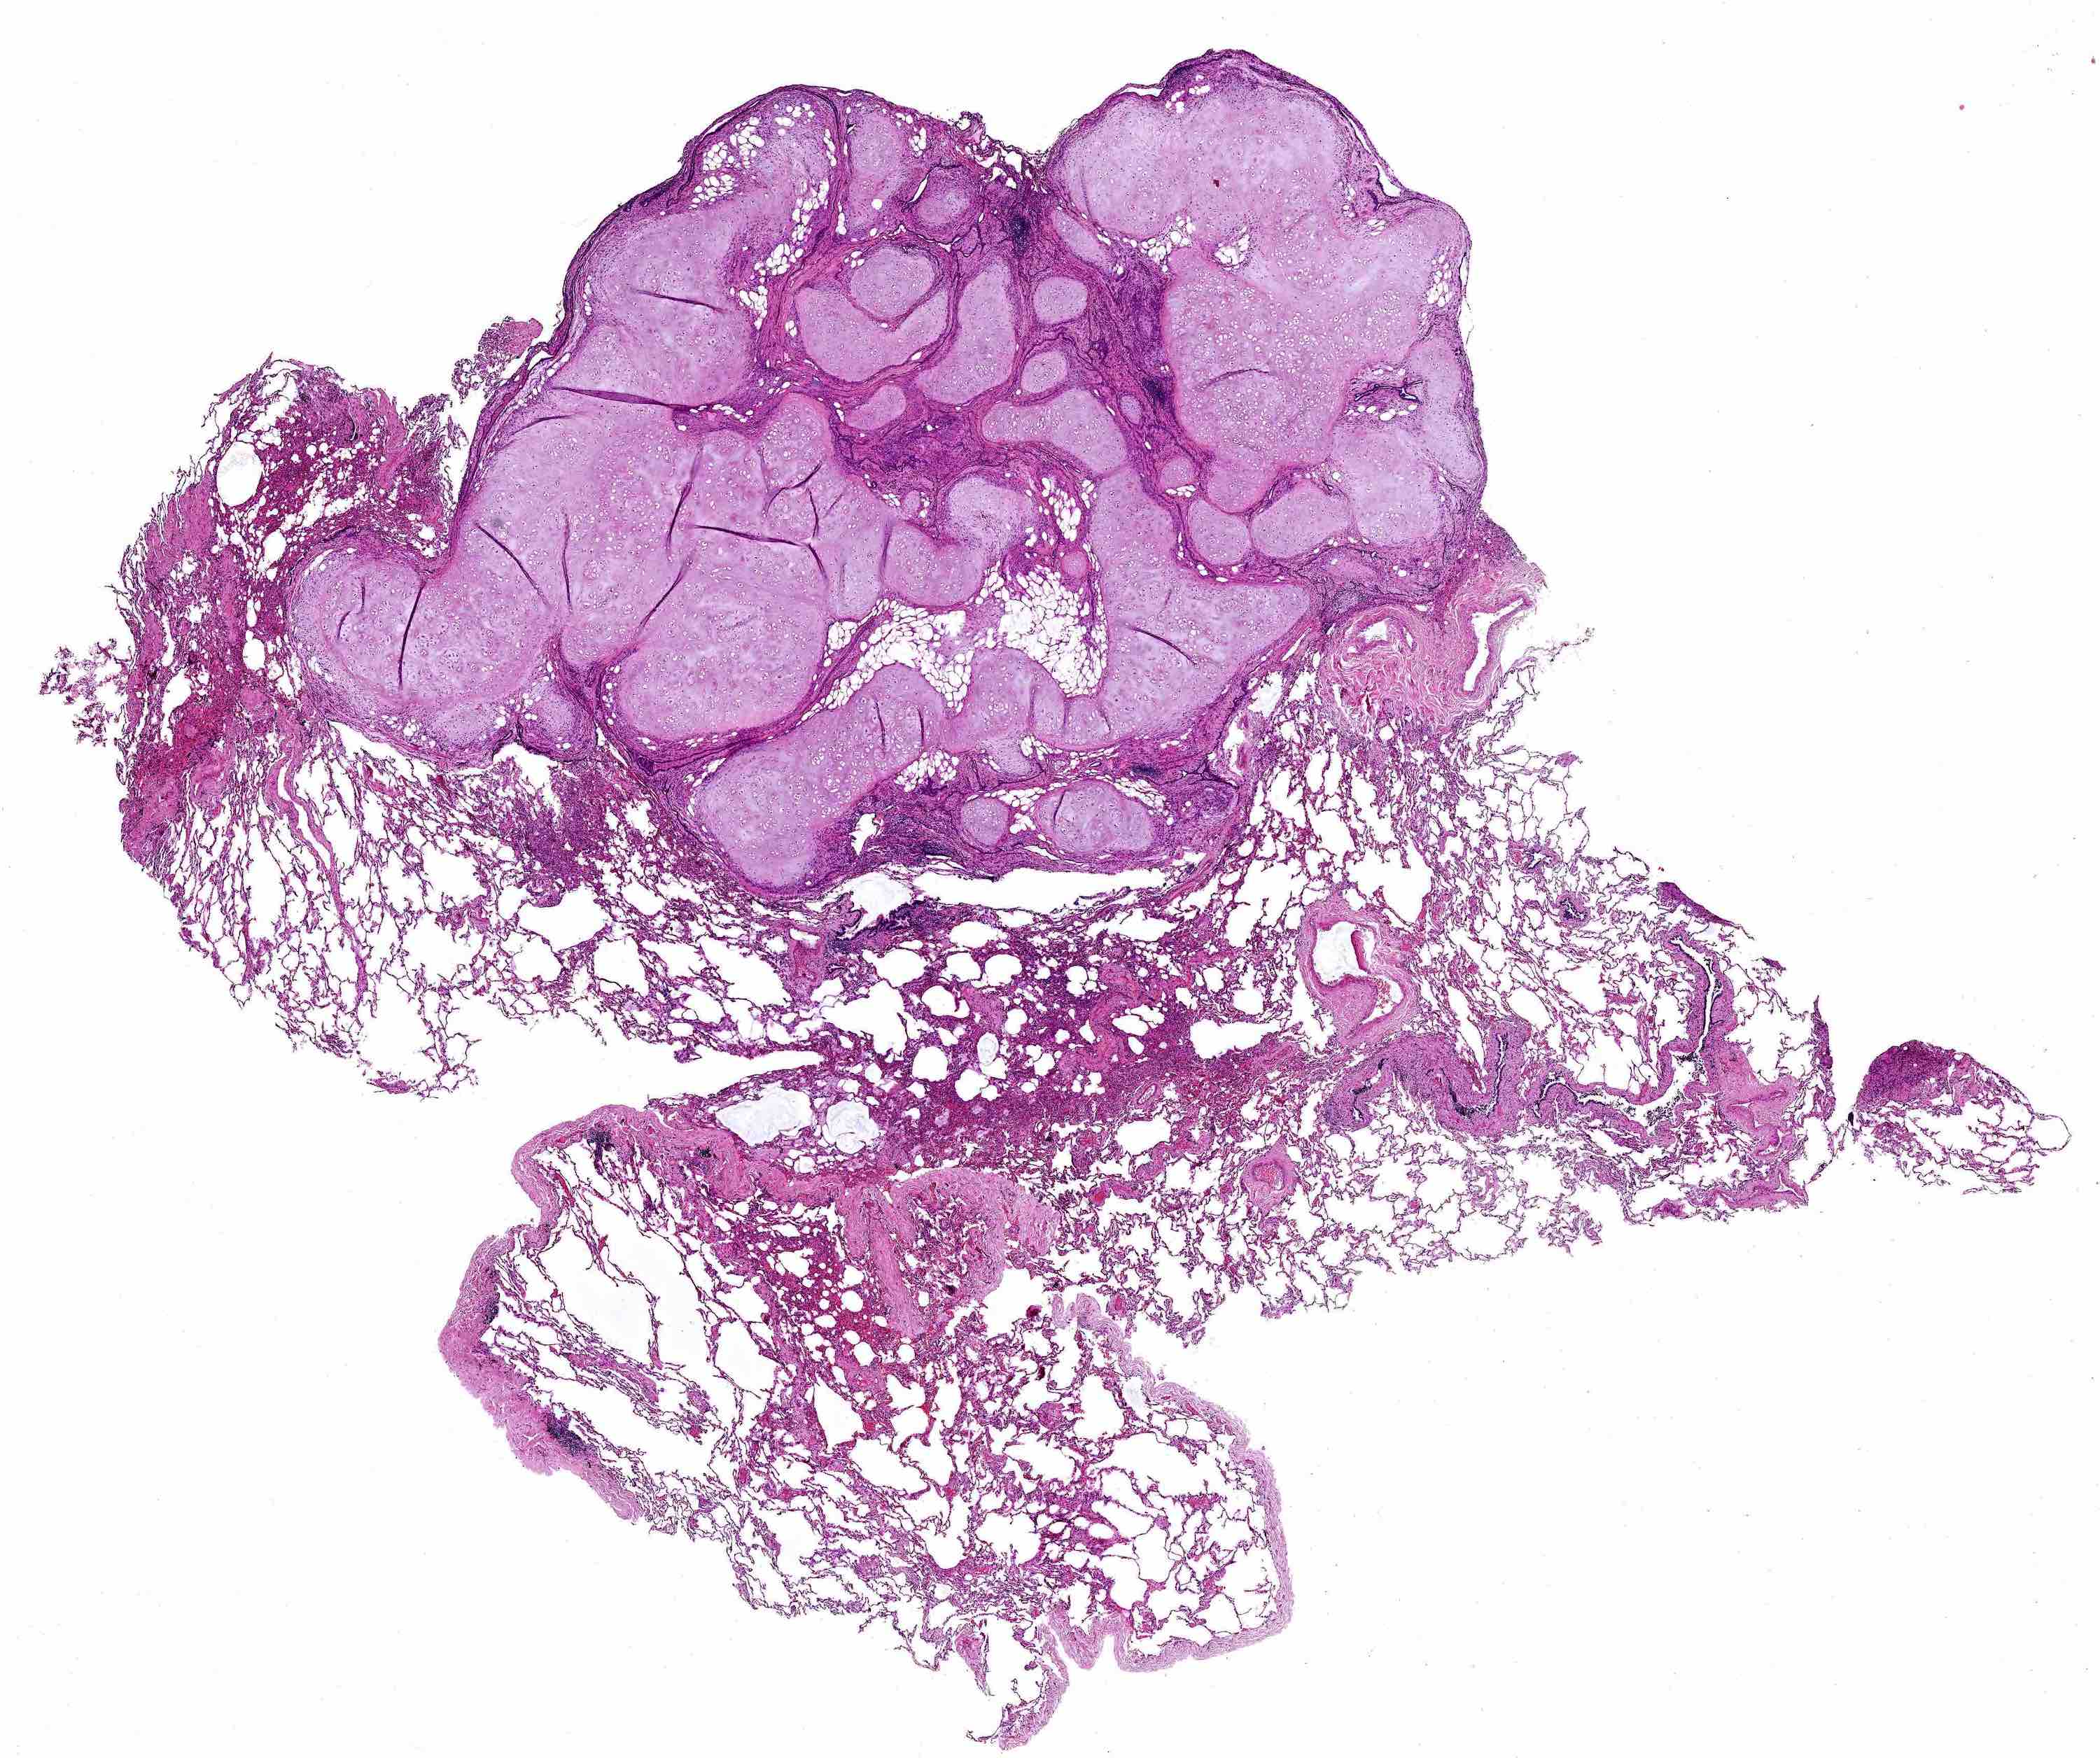

Microscopic (histologic) description

- Composed predominantly of varying degrees of mesenchymal tissue: hyaline cartilage, fat, smooth muscle and bone

- Other connective tissue elements may be present, represented by bland spindle cells, fibrous tissue or myxoid change

- Variably conspicuous, entrapped benign epithelial cells

- Reference: Thorax 1987;42:790

Microscopic (histologic) images

Contributed by Hui-Hua Li, M.D., Ph.D. and Jefree J. Schulte, M.D.

Contributed by @Andrew_Fltv on Twitter